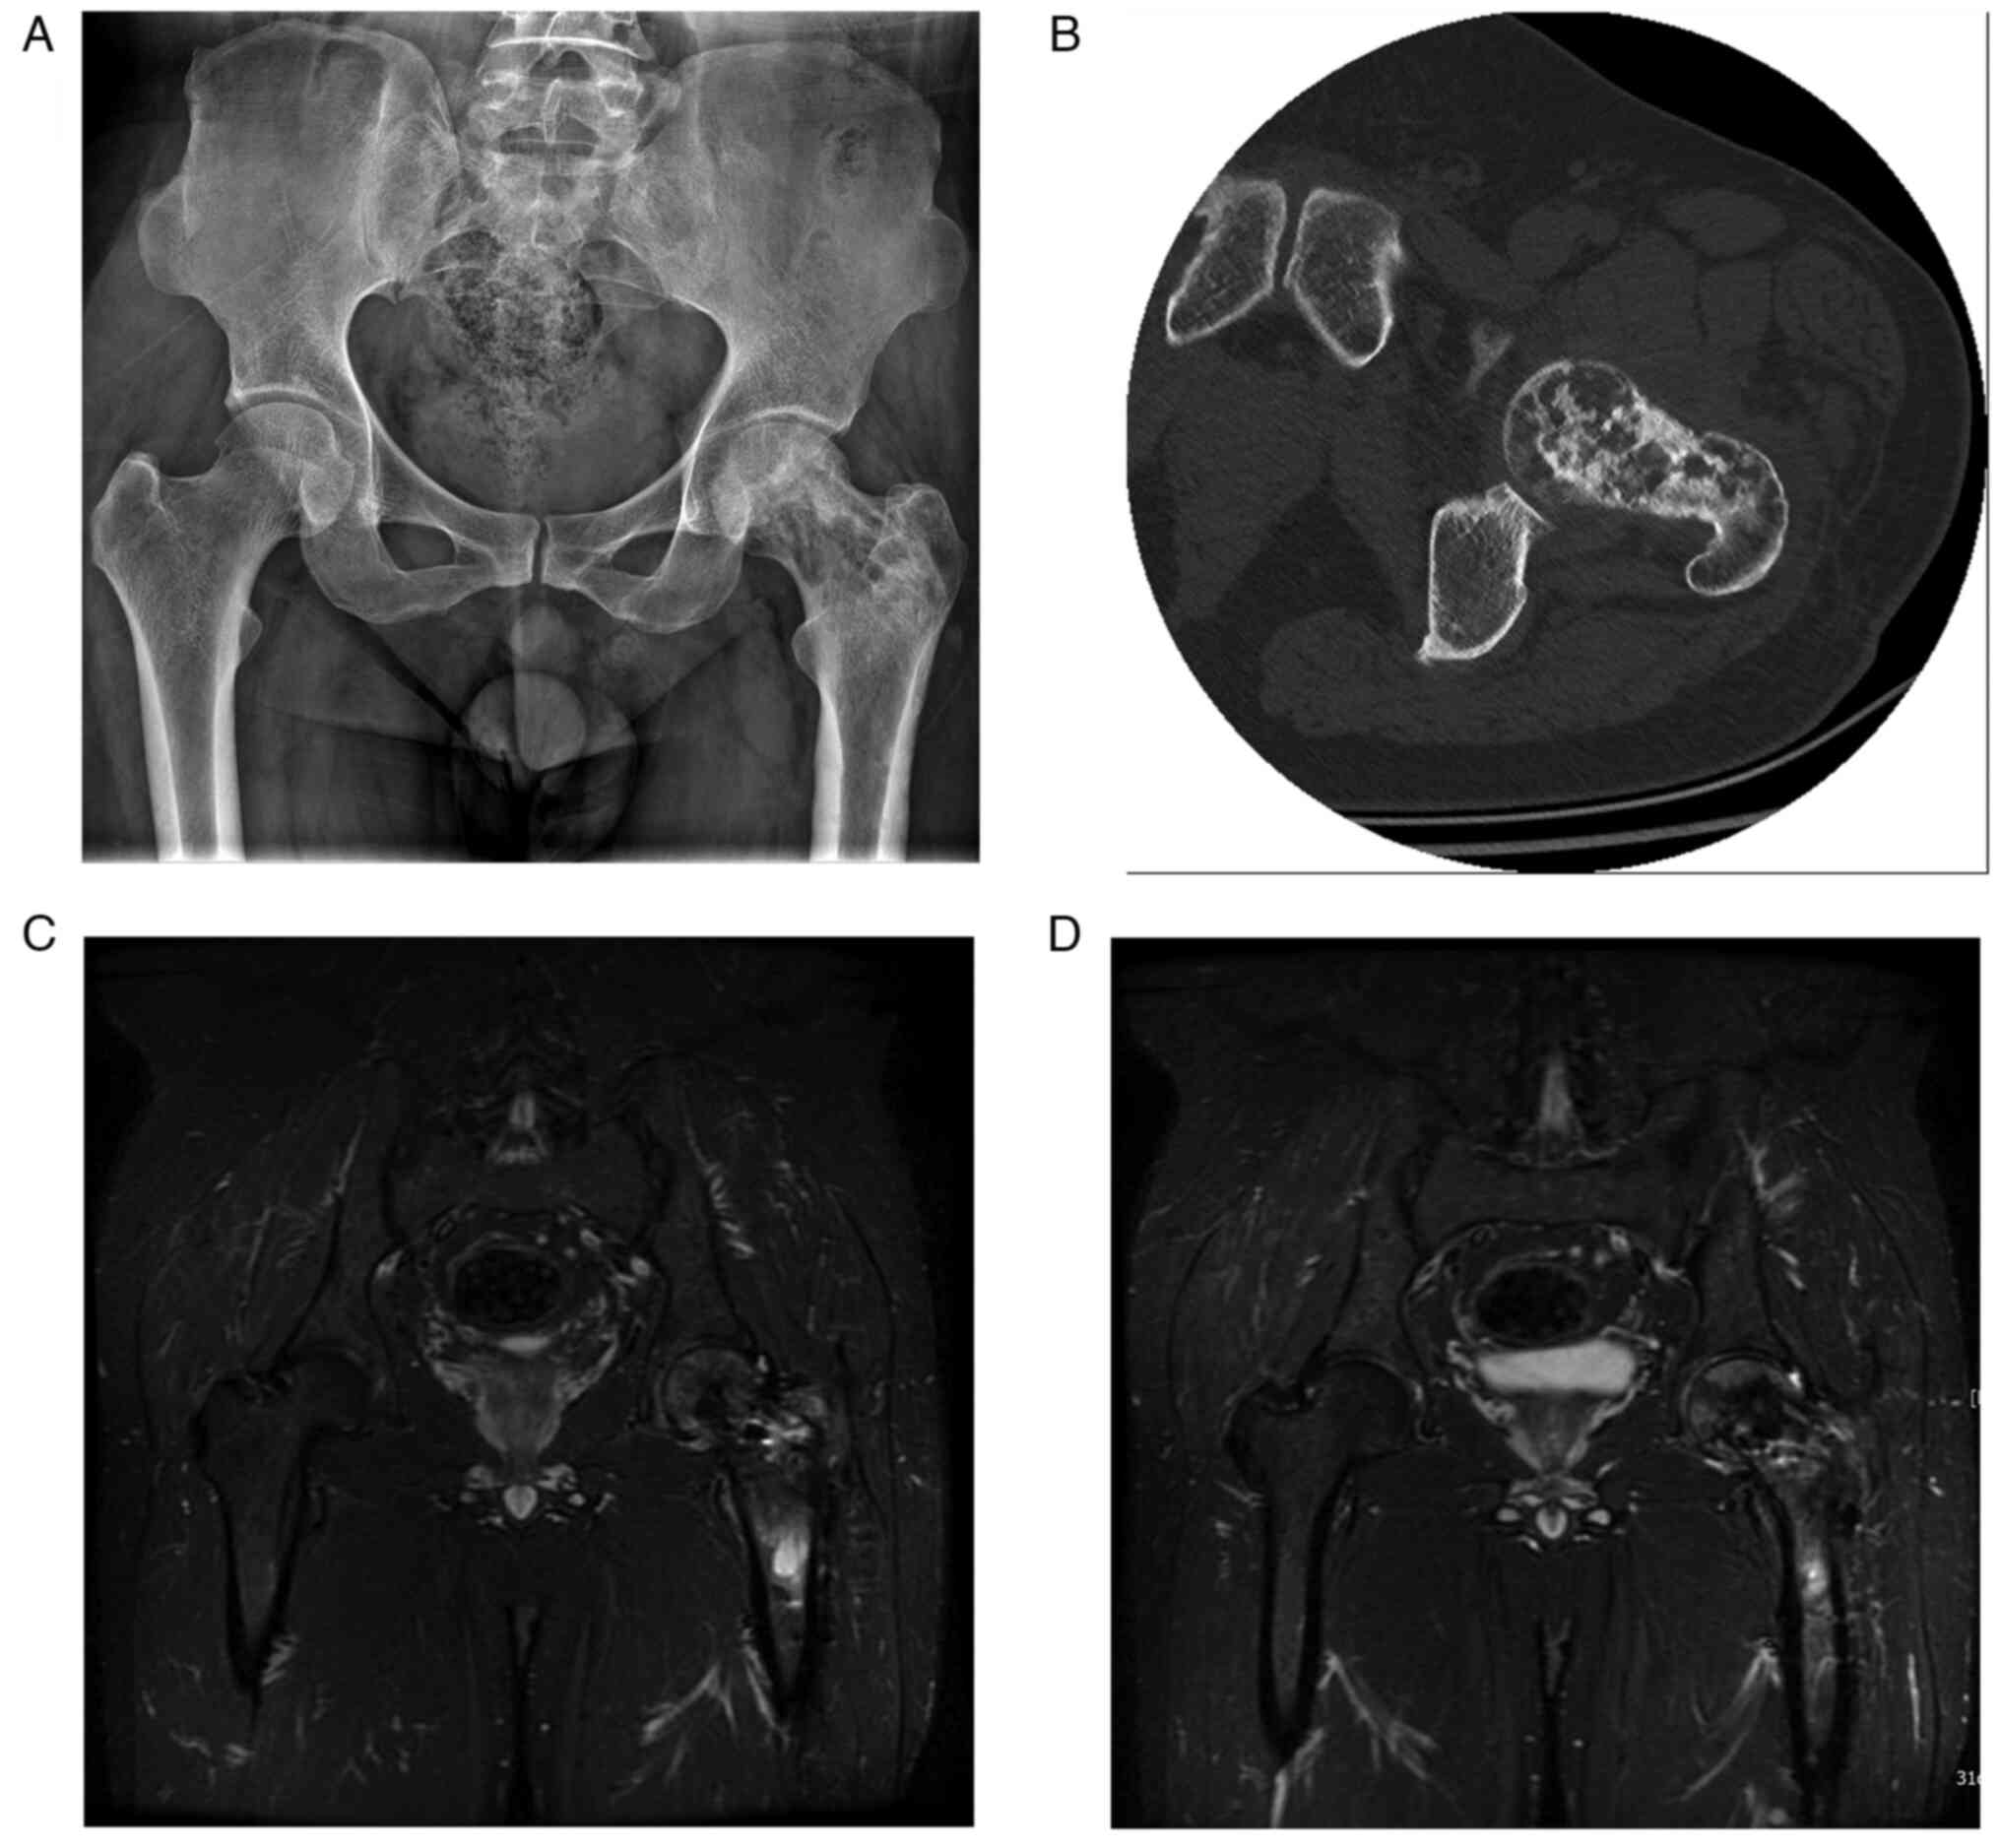

Malignant transformation of an aneurysmal bone cyst of the femoral neck: A case report

Aneurysmal bone cyst (ABC) is a benign, distending, osteolytic and locally aggressive bone tumor that is mostly associated with trauma. Approximately 1% of bone tumors are ABCs, which are most prevalent in adolescents and are usually detected in the spine and long tubular bones. The diagnosis of ABC mainly relies on histopathology, malignant transformation is rare, and the chance of malignancy increases if there are multiple recurrences. Due to the rarity of reports of malignant transformation of ABCs into osteosarcoma, there is still considerable debate on the appropriate treatment strategy. The current paper presents a case of aneurysmal bone cyst malignant to osteosarcoma and the therapeutic measures to provide expertise for the diagnosis and treatment of ABCs that are malignant to osteosarcoma.